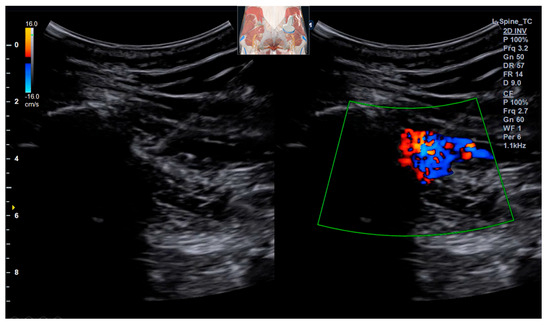

Background: Deep gluteal syndrome (DGS) is an underdiagnosed cause of sciatica-like pain, involving the entrapment of the sciatic nerve by various structures within the subgluteal space. While cases of ossification or calcification in the context of severe pelvic imbalance have been rarely reported, isolated SSL calcification as a primary cause of DGS remains largely unexplored and undocumented. This case report presents the first documented instance of sacrospinous ligament (SSL) calcification identified as the primary cause of DGS and its successful management with ultrasound-guided prolotherapy. Case Presentation: A 51-year-old female presented with severe, worsening left-sided sciatica of several months’ duration. Physical examination revealed an antalgic gait, positive sacroiliac joint tests, and multiple positive DGS-specific provocative tests (FAIR, Pace sign, Seated Piriformis Stretch). Radiographs and musculoskeletal ultrasound (MSK-US) confirmed calcification within the left sacrospinous ligament, with associated sciatic nerve swelling. The patient underwent three sessions of ultrasound-guided prolotherapy (dextrose 10% with lidocaine) targeting the calcification site, followed by a structured rehabilitation program. Results: The patient reported a significant reduction in pain, from a Visual Analog Scale (VAS) score of 10/10 to 1/10 within one month. All previously positive provocative tests converted to negative, indicating a resolution of the nerve entrapment. Functional mobility was fully restored. Conclusions: This case highlights isolated sacrospinous ligament calcification as a potential and previously overlooked pathological entity responsible for deep gluteal syndrome. To our knowledge, this is the first report to implicate ligamentous calcification as a primary etiological factor in DGS. Musculoskeletal ultrasound proved indispensable for both diagnosis and treatment guidance. Furthermore, ultrasound-guided prolotherapy emerged as a successful and minimally invasive therapeutic option in this case, potentially by stabilizing the ligament and reducing neurogenic inflammation. This case expands the differential diagnosis of sciatica, introduces a new target for intervention in refractory cases, and underscores the need for future studies in larger patient cohorts to validate these findings. Full article

Figure 1